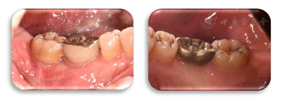

术后2年,47牙龈无明显红肿,远中及颊侧中央PD 3~4 mm,BI1,颊侧中央附着龈宽约2 mm,颊侧中央根面无退缩,患者的咬合无不适(图20,图21)。